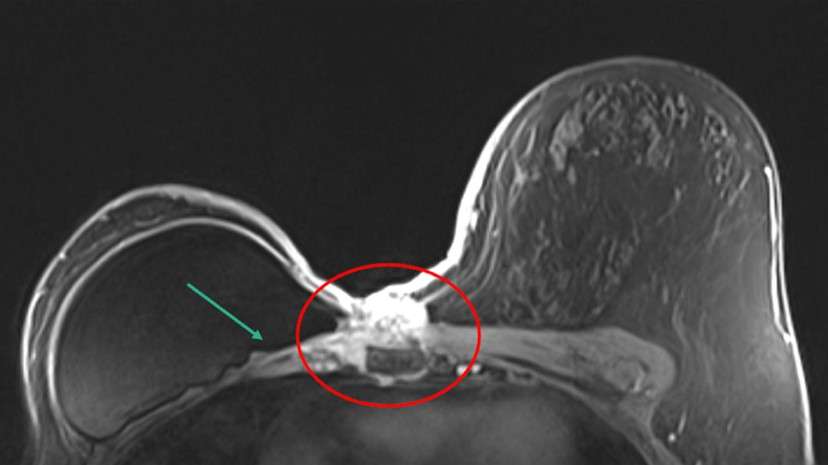

Case 2: Patient with history of right breast cancer status post right mastectomy presenting with skin erythema. Patient underwent diagnostic MRI which demonstrated the following (Figure 3).

The patient was diagnosed with invasive ductal carcinoma and treated with neoadjuvant chemotherapy.